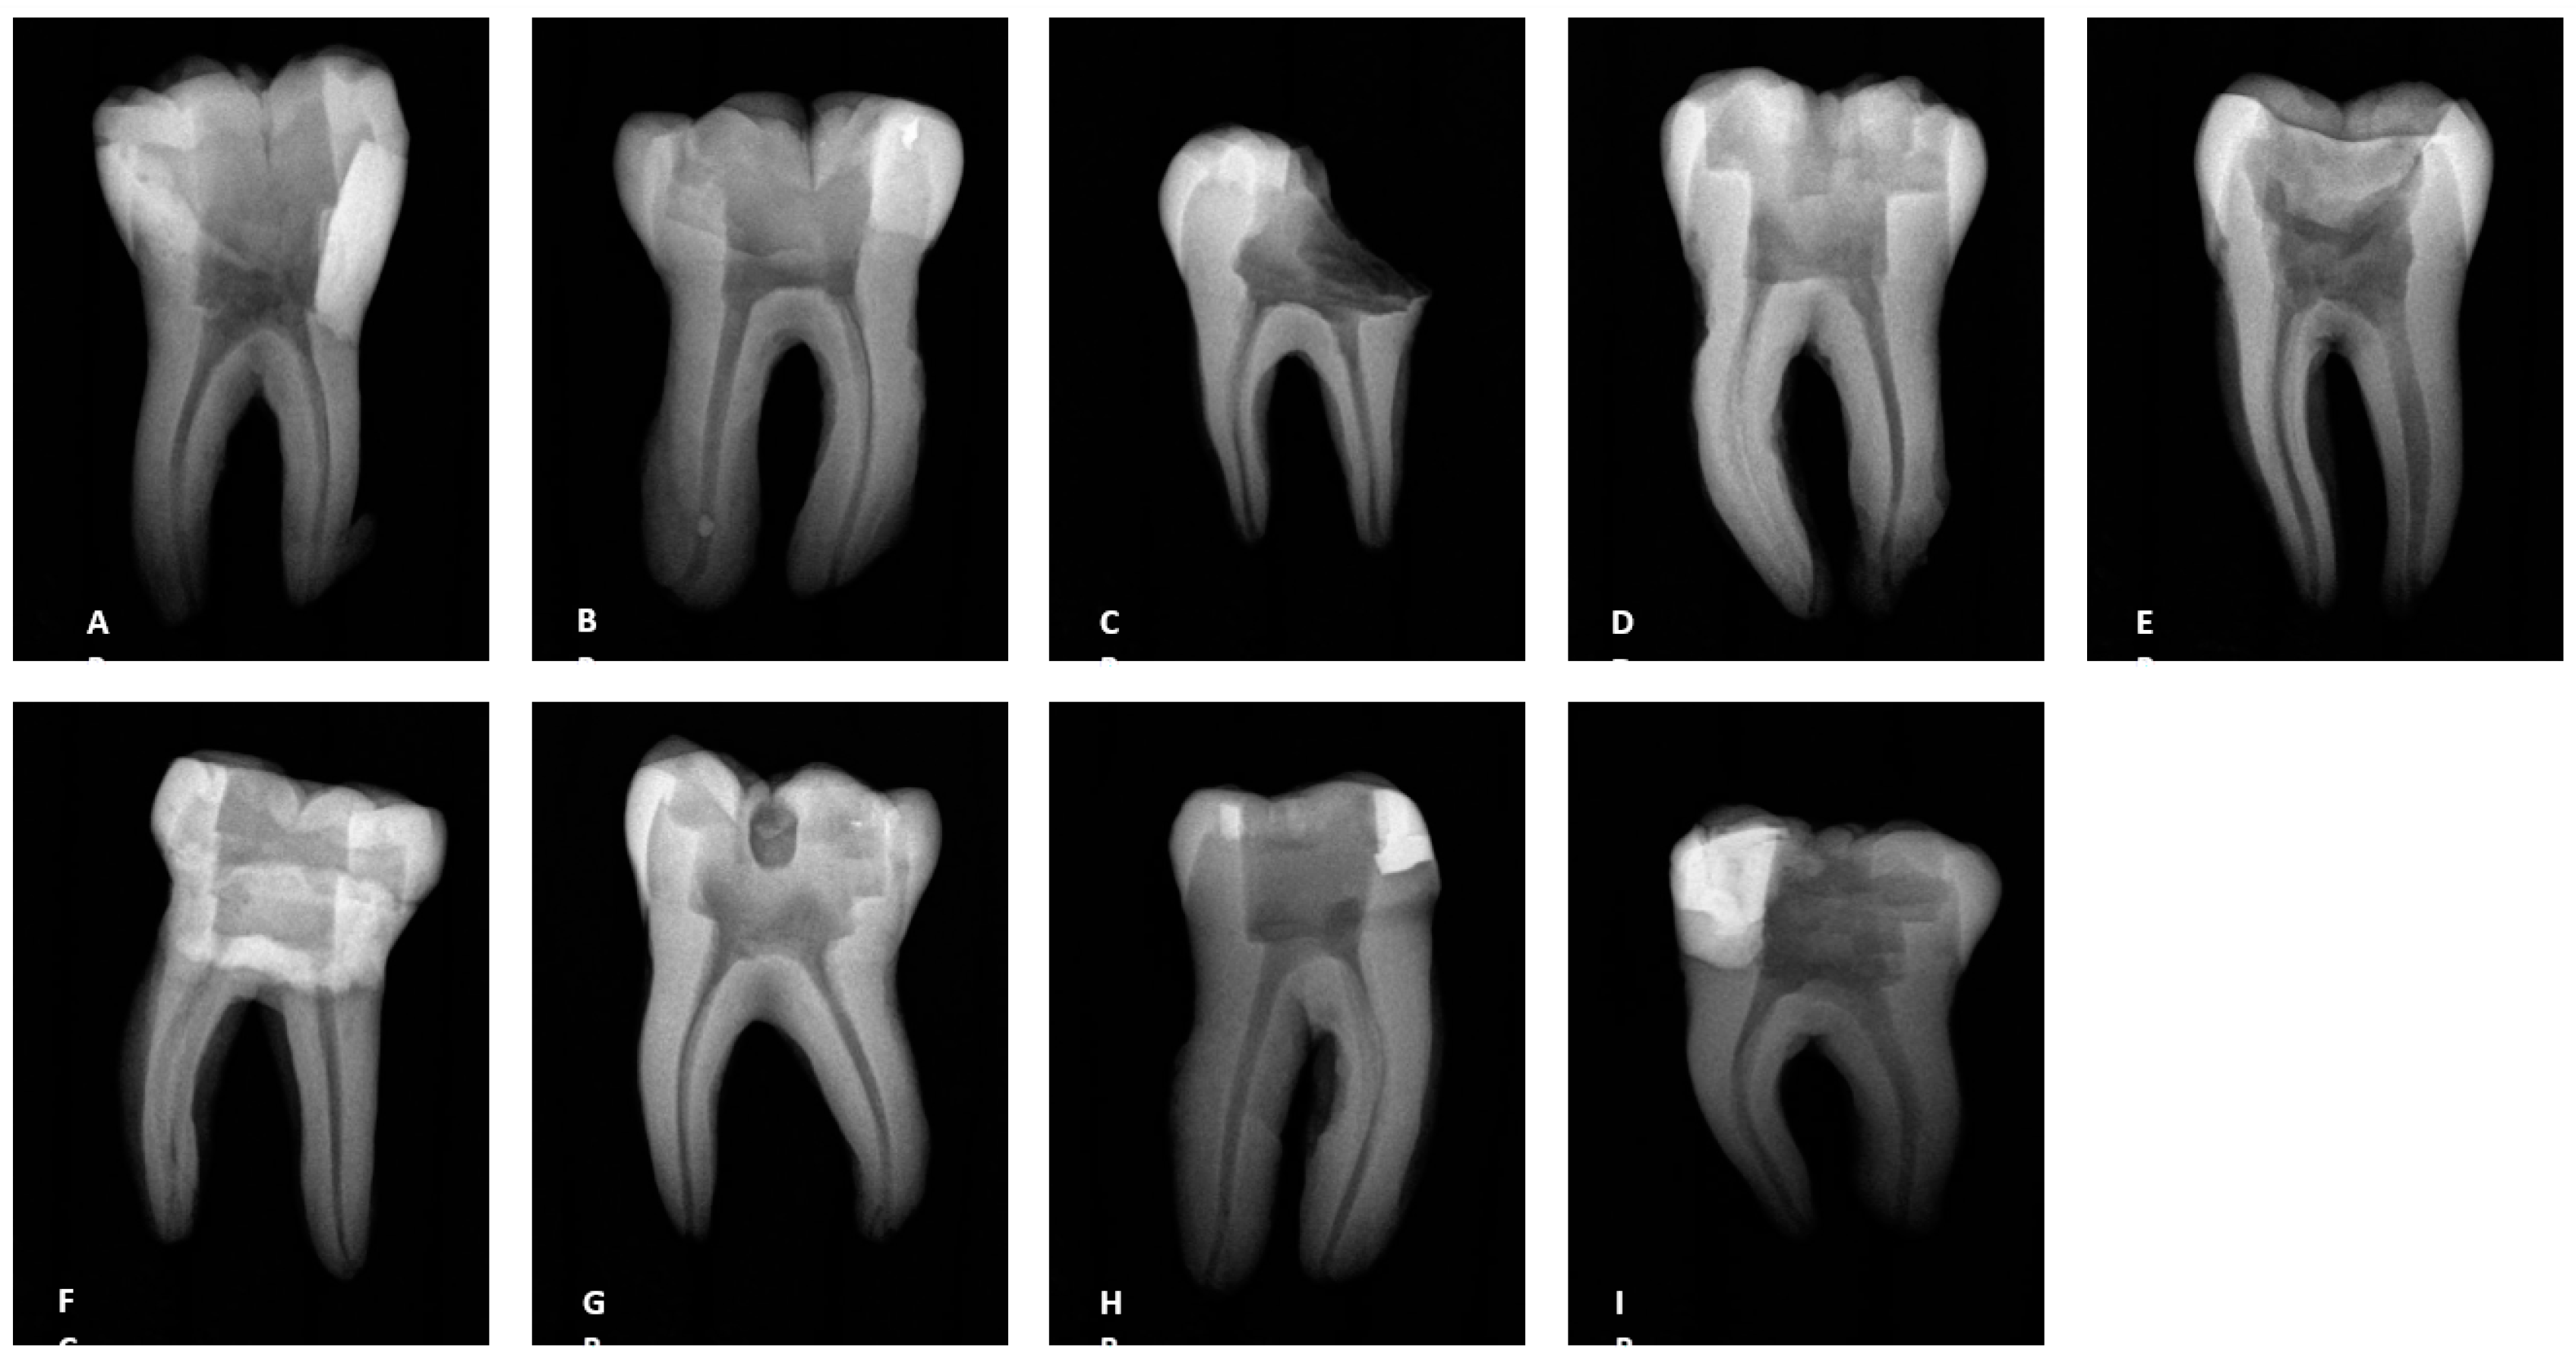

3.2. Radiographs